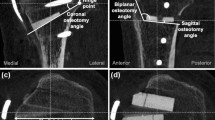

The HTO model, with medial TomoFix plate and without LHF, used in a previous study was modified according to various hinge fractures. The angle of the medial open wedge and the width of the lateral hinge were set to 12° and 10 mm, respectively. The width of the lateral hinge refers to the distance from the apex of the wedge to the lateral edge of the tibia. In this study, three types of LHF fractures, namely type 1 (T1), type 2 (T2), and type 3 (T3), were created according to the Takeuchi classification [20]. T1 fracture referred to a crack, parallel to the osteotomy line of the open wedge, in the open wedge extending to the proximal site of the tibiofibular joint. T2 fracture referred to a crack in the open wedge extending downwardly to the distal site of the tibiofibular joint. T3 fracture was a lateral plateau fracture, which referred to a crack upwardly to the lateral plateau of the proximal tibia (Fig. 1). The fractures were created with virtual planes using the CAD software SOLIDWORKS 2019 (Dassault Systemes SolidWorks Corp., Waltham, MA, USA). Hence, the fracture surfaces were simplified as planes, and no gap existed at the fracture sites. The micro-geometry of the fractured surface was not considered. Then, different fixation strategies were used to stabilize each fracture type (Fig. 2), including medial plating (MP) with the original TomoFix plate (TomoFix, DePuy Synthes, Oberdorf, Switzerland), bilateral plating (BP) with medial TomoFix plate and proximal lateral tibia locking plate (LCP, proximal tibia plate, DePuy Synthes, Oberdorf, Switzerland), and BP without the locking screw (BPWDS) at the proximal combi hole (D-Hole) of the TomoFix plate. The length and width of the TomoFix plate were 115 and 16 mm, respectively. The thickness of both medial TomoFix and lateral locking plates was set to 3 mm. The lengths of the screw at the proximal tibia (including the D-hole screw) and tibia shift in the MP were 56 and 26 mm, respectively. However, the length of the D-hole screw in the BP group was reduced to 38 mm to dodge the proximal screw of the lateral locking plate. The length of the proximal screw for the lateral locking plate was 56 mm (top row) and 44 mm (second and third row from the top) (Fig. 2b, c). The screw length for the lateral locking plate at the tibia shift was 26 mm. The diameter of all screws was set to 5 mm.